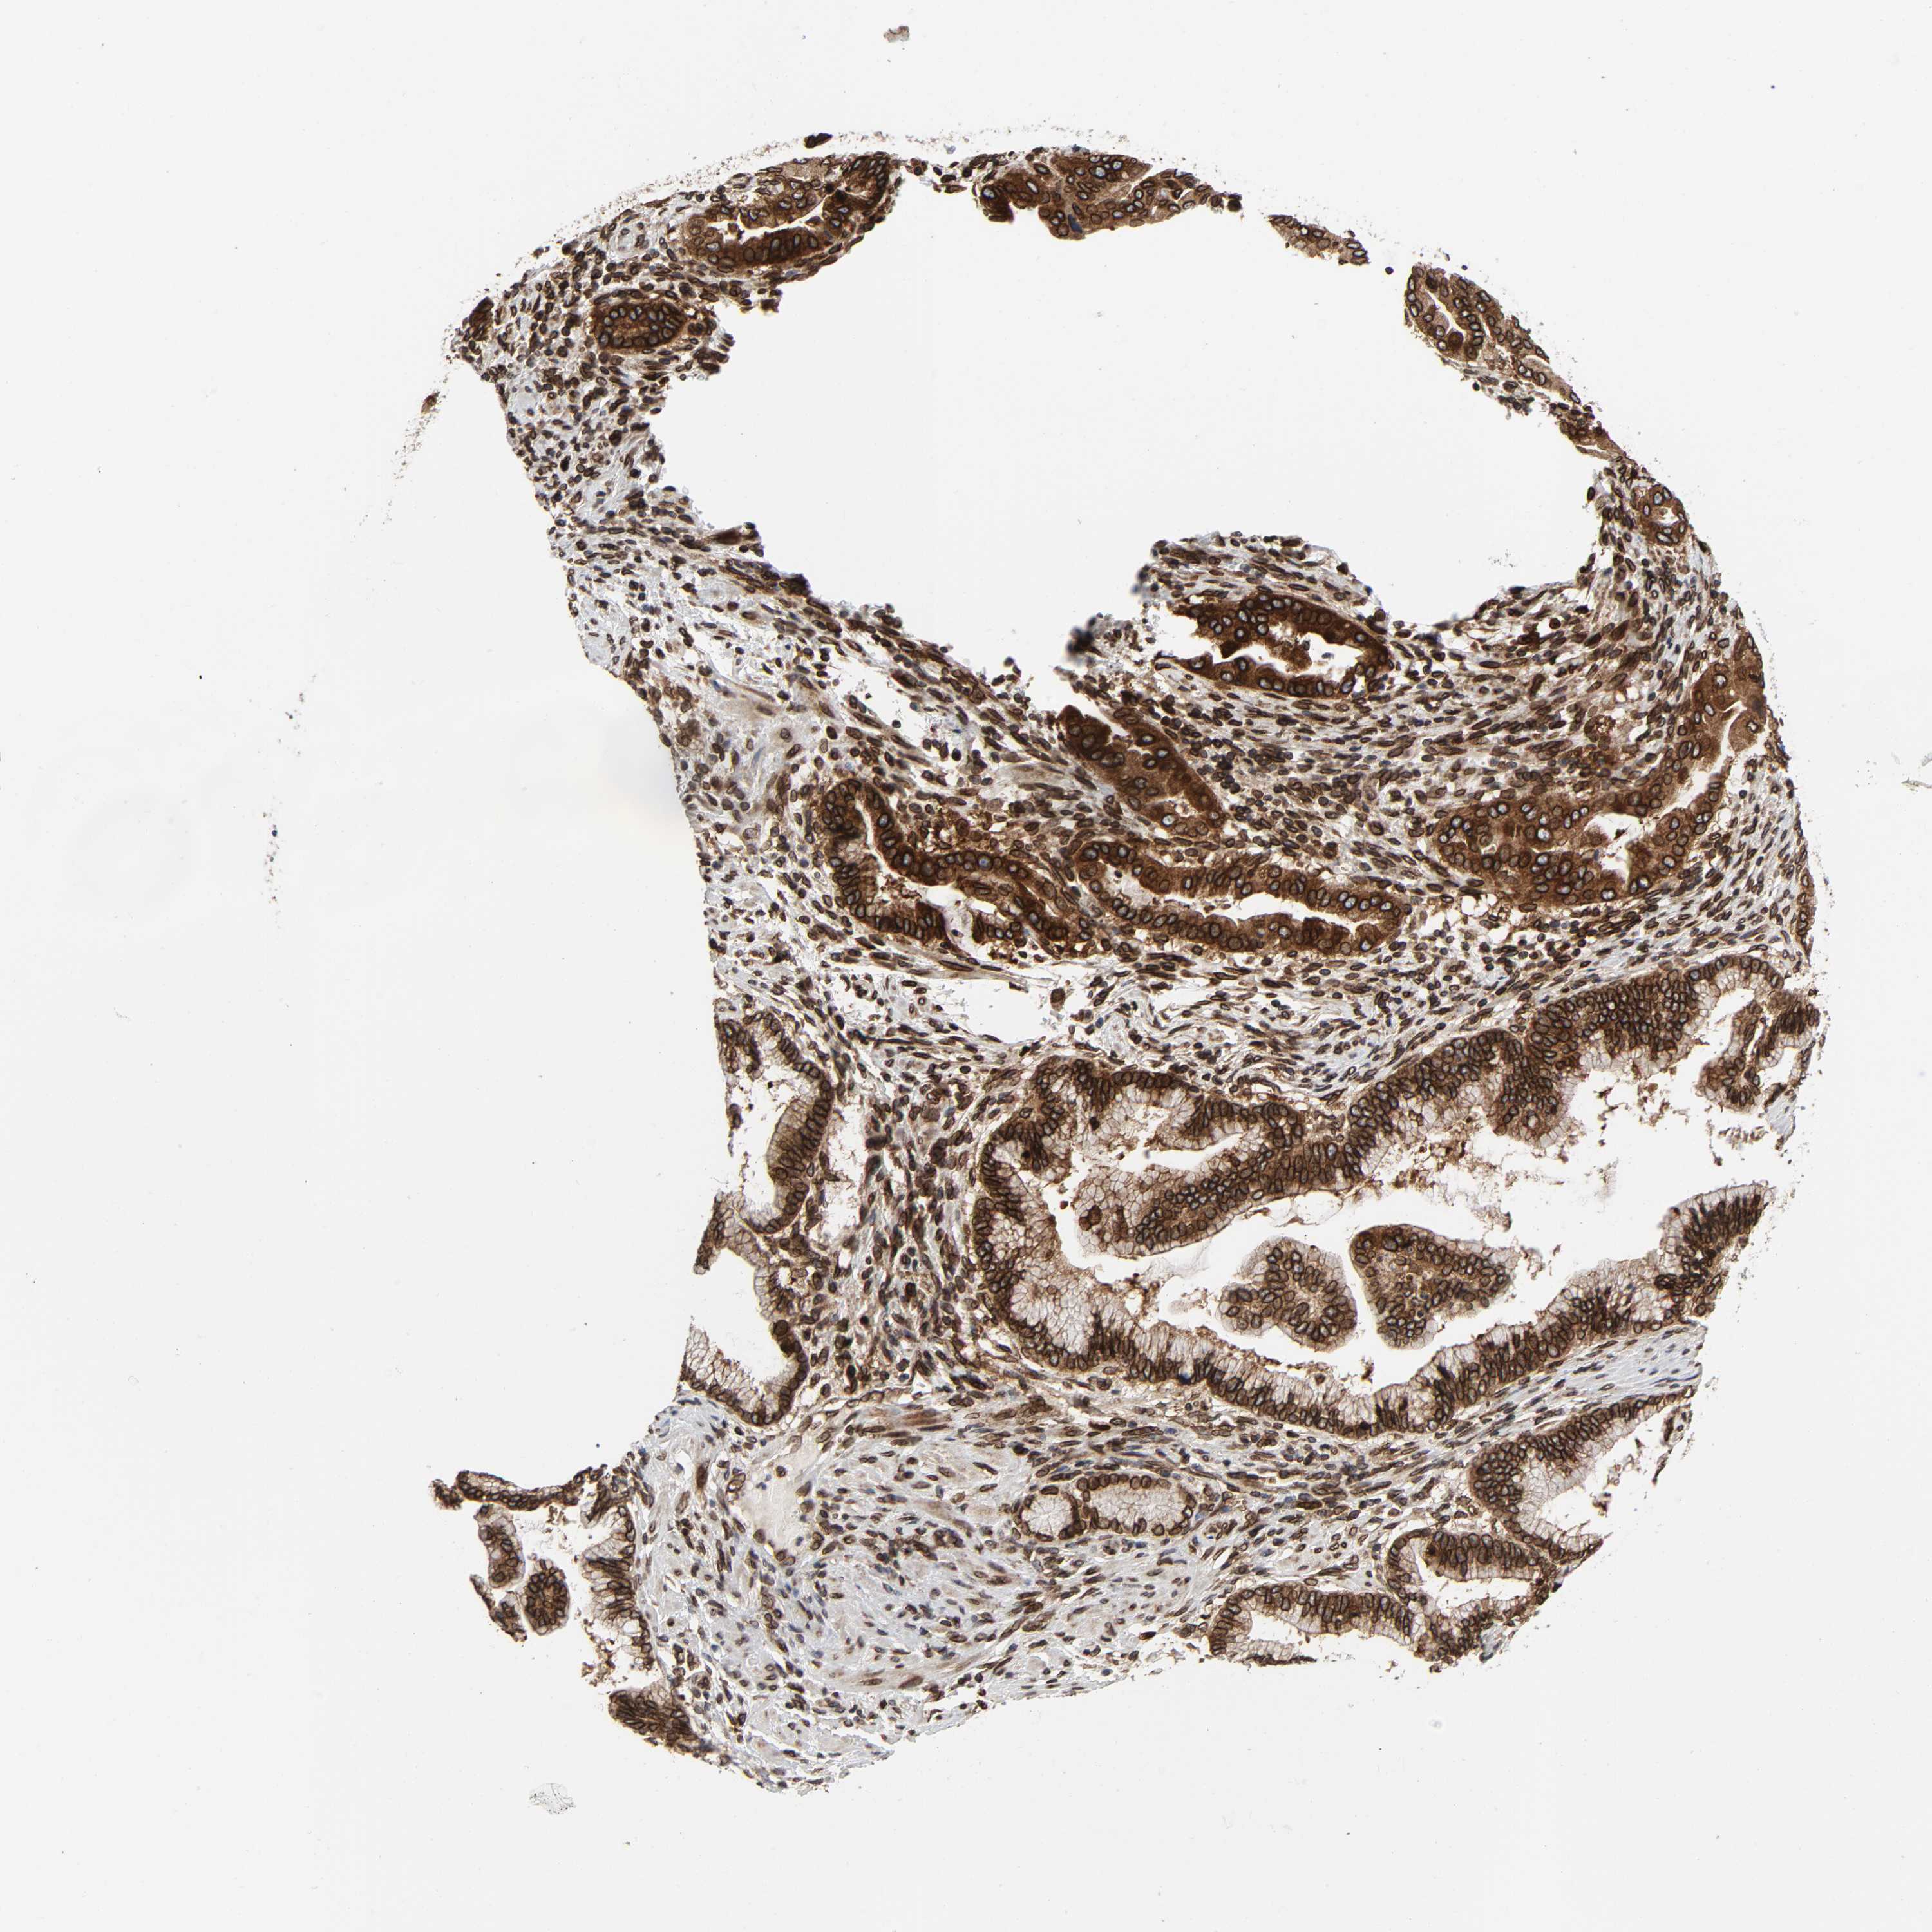

PANCREATIC CANCER - Protein expressioni

A mouse-over function shows sample information and annotation data. Click on an image to view it in a full screen mode. Samples can be filtered based on level of antibody staining by selecting one or several of the following categories: high, medium, low and not detected. The assay and annotation is described here.

Note that samples used for immunohistochemistry by the Human Protein Atlas do not correspond to samples in the TCGA dataset.

Antibody stainingi

Antibody staining in the annotated cell types in the current human tissue is reported as not detected, low, medium, or high, based on conventional immunohistochemistry profiling in selected tissues. This score is based on the combination of the staining intensity and fraction of stained cells.

Each image is clickable and will lead to virtual microscopy that enables deeper exploration of all samples and also displays staining intensity scores, fraction scores and subcellular localization as well as patient and tissue information for each sample.

Antibody HPA050110

Antibody CAB004293

Adenocarcinoma, NOS

Adenocarcinoma, metastatic, NOS